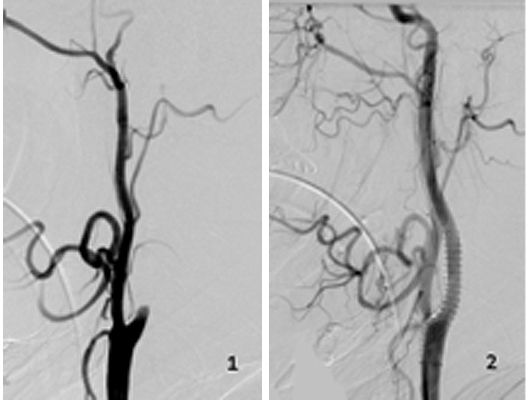

Mit den modernen Verfahren zur Wiedereröffnung von verschlossenen Blutgefäßen können wir Patienten mit Schlaganfall in vielen Fällen helfen. Das folgende Beispiel zeigt die angiographischen Bilder eines Patienten, der mit vollständiger Lähmung der rechten Körperhälfte und einer schweren Sprachstörung eingeliefert wurde. Ursächlich zeigte sich ein Verschluss der linken Halsschlagader, vermutlich auf dem Boden einer arteriosklerotischen Einengung (Bild 1). Das Gefäß wurde daraufhin mit einem Stent wiedereröffnet (Bild 2). Zusätzlich zeigte sich ein Verschluss der Endstrecke des Gefäßes durch Blutgerinnsel (Bild 3). Diese konnten vollständig entfernt werden (Bild 4). Der Patient erholte sich nach der Behandlung innerhalb weniger Tage vollständig.

Das Beispiel zeigt die angiographischen Bilder einer Patientin, bei der es zu einer Sehstörung gekommen war. Die Ursache war ein großes Aneurysma der Halsschlagader an der Schädelbasis (Bild 1). Bild 2 zeigt die Lage des Aneurysmas hinter dem Auge. Durch den Druck des Aneurysmas auf den Sehnerv war es zu der Sehstörung gekommen. Die Patientin wurde mit einer speziellen Gefäßprothese versorgt, welche über eine Punktion der Leistenarterie in die Halsschlagader eingesetzt wurde (Bild 3). Bei der Kontrolle nach 6 Monaten zeigte sich ein vollständiger Verschluss des Aneurysmas (Bild 4). Die Sehstörung hatte sich vollständig zurückgebildet.